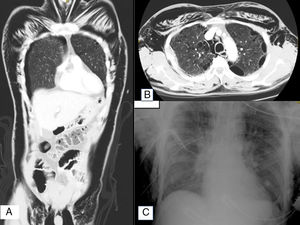

A 57-year-old male with a history of spontaneous pneumothorax 23 years ago was admitted to the Intensive Care Unit following high-energy trauma to the right side of the chest (hit by a car while bicycling). Upon arrival, crepitants were noted from the ocular zone (the patient being unable to open the eye and presenting great dysphonia) to the scrotum and root of the thigh. The patient was stable from the hemodynamic and respiratory perspective, and a full-body CT scan was made, revealing subcutaneous emphysema occupying practically the entire thoracic and abdominal zone, with the dissection of neck muscle layers (Fig. 1A) Bullae were observed in both lung vertexes (Fig. 1B), with multiple right rib fractures. Oxygen therapy and analgesia were provided, and two pleural drains were placed, followed by improvement of the subcutaneous emphysema (Fig. 1C). The clinical course proved favorable, and the patient was discharged from intensive care after a stay of 96h.